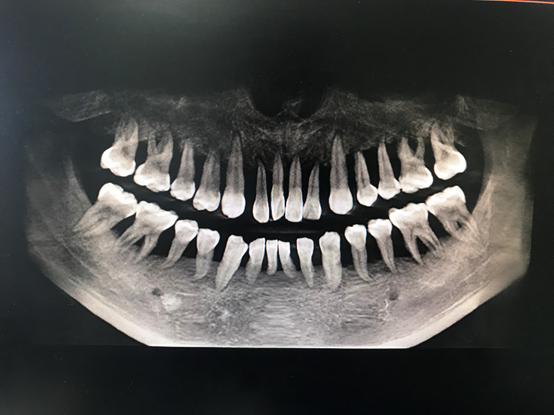

近日,25歲的小周碰到了一個大難題,他的牙“出問題了”,全口牙齒無法咀嚼,除了流食以外什么也不能吃。杭州師范大學附屬醫(yī)院牙周病診療中心醫(yī)生發(fā)現(xiàn),小周的牙齒情況類似于80歲的老太太,全口牙齒幾乎都是松動無法行使咀嚼功能。這意味著小周口內(nèi)牙齒幾乎都要拔除,全口牙沒有幾個能保留。

“我從醫(yī)這么多年也是第一次見到如此嚴重的牙周炎患者?!苯釉\醫(yī)生周矗說,從小周的口腔檢查中發(fā)現(xiàn),他的全口牙齒都有牙齦的膿腫,伴有嚴重的骨頭萎縮以及吸收,所有牙齒幾乎都是3度松動,并且口腔異味特別嚴重,牙齒上附著大量牙結石及食物軟垢。